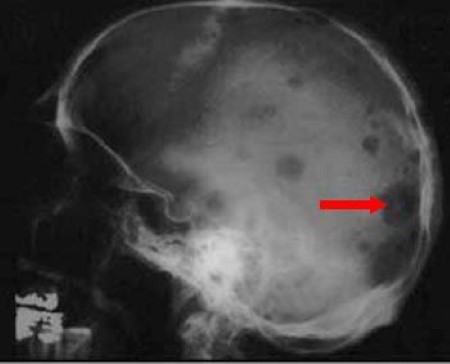

X-ray of multiple myeloma in skull

A skull X-ray taken from the side shows typical findings of multiple myeloma and multiple "punched-out" holes. The arrow is pointing at one of the larger holes.